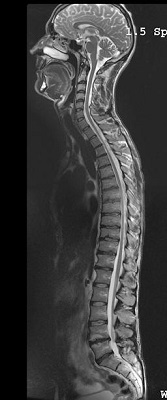

Figure 1. Spine pasted image from two locations

Pasting applications include spine, peripheral vascular and whole body oncology screening.